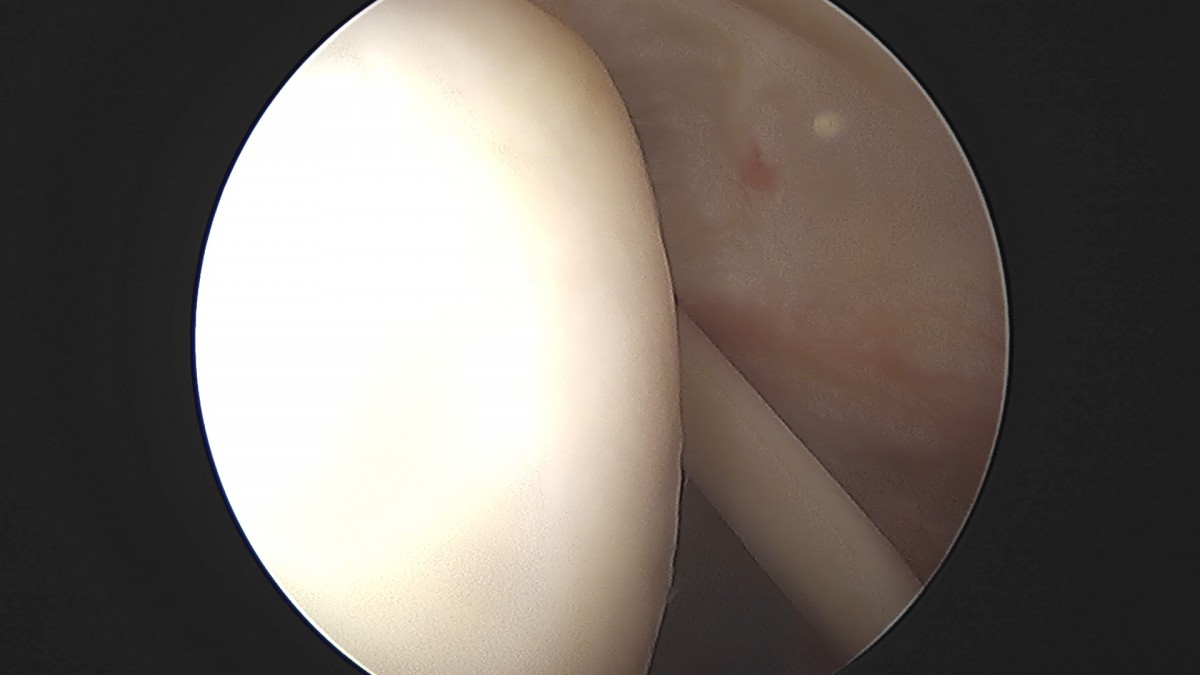

이재상원장님 어깨 견봉하 감압술 및 관절낭 이완술 양명O 환자

dae765e4d9ac96aee867c9d6292d8784_1758004380_2675.jpg